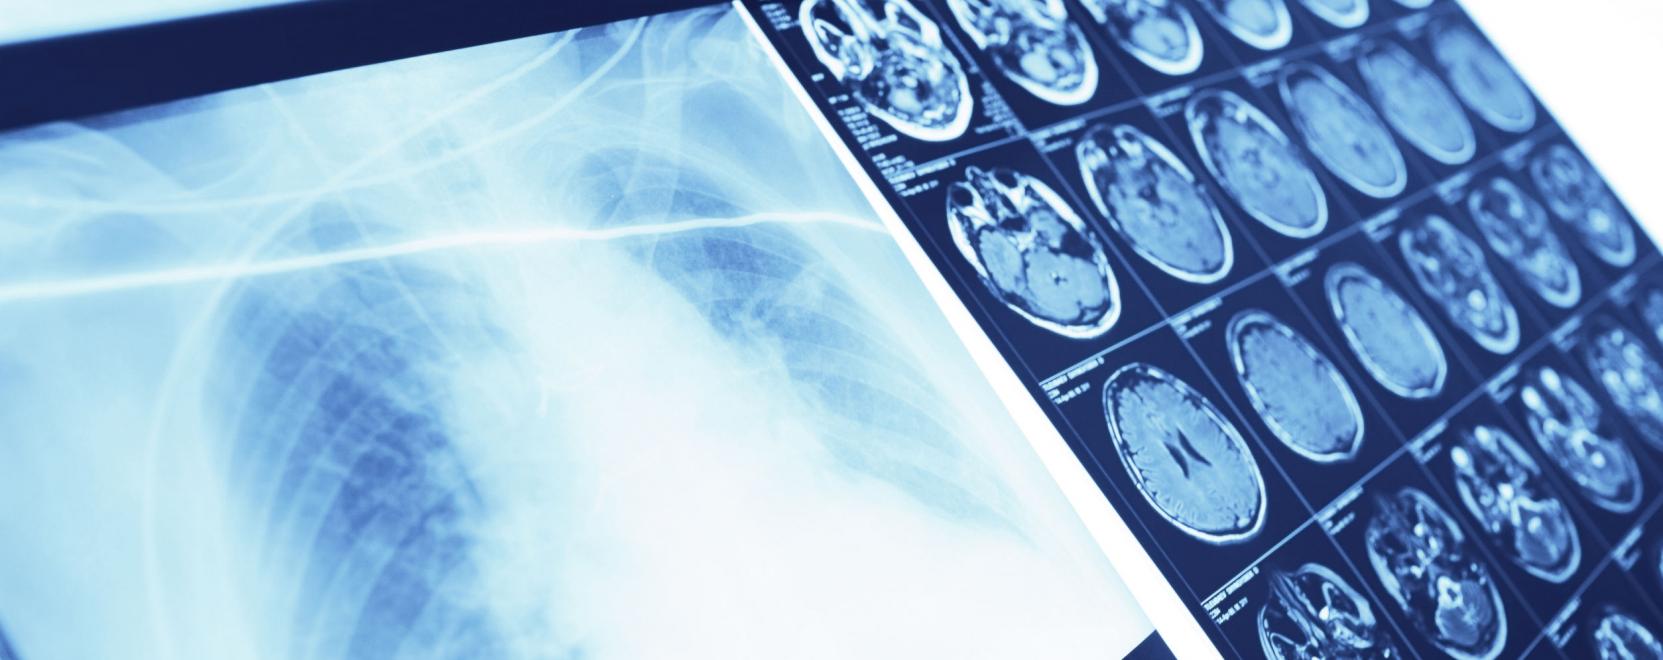

Az Alibaba rendszere a tüdőgyulladásokról készült CT-felvételeket elemzi. A neurális hálót 5 ezer beteg tüdőfelvételével tréningezték.

A vállalat szerint az új mesterséges intelligencia technológia akár 96 százalékos pontossággal képes felismerni a koronavírusos betegekre jellemző vírusos tüdőgyulladást. Az algoritmus a betegek tüdejéről készült CT-felvételeket elemzi, ehhez mindössze 20 másodpercre van szüksége. Ez komoly könnyebbséget jelenthet a túlterhelt egészségügyi személyzetnek, hiszen egy doktornak egy felvétel elemzése akár 15 percet is igénybe vehet – állítja a beszámoló.

A világjárványt okozó fertőzés diagnosztizálására más megoldások is születtek. A Ping An cég nemrég jelentette be, hogy az intelligens képalkotó-diagnosztikus rendszerüket ingyen bocsátotta több mint 1500 orvosi intézmény rendelkezésére. Az ötezernél is több eset elemzése állítólag betegenként átlagosan 15 másodpercig tartott, a diagnózis 90 százalék feletti pontosságúnak bizonyult.